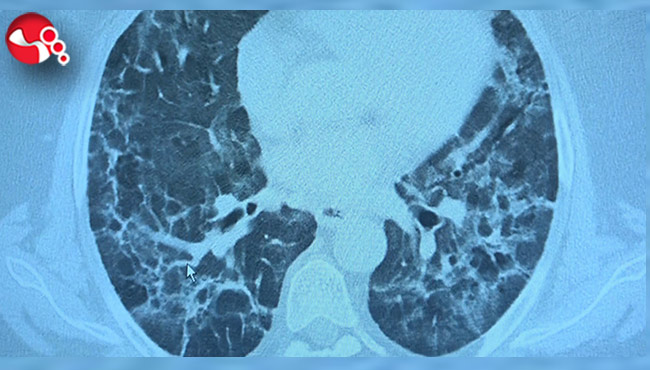

Kliniğe gelen kişilerin akciğer tomografilerine inceleyen Prof. Dr. Özkaya, "62 yaşında bir teyzemiz 11 Mart'ta yoğun bakımda solunum yetmezliği ile hastaneye yattığında hayati tehlikesi vardı ve Covid- 19'u atlattı. Yalnız aradan 3 ay geçmesine rağmen hala akciğerinde Covid - 19'un uzamış etkileri dediğimiz sekel lezyonları var. Bu hasta nefes darlığı çekiyor. Diğer bir vaka örneği verirsek, 62 yaşında bir erkek hasta. Mart'ın sonlarında geldiğinde röntgeninde küçücük buzlu camları vardı. Birden Nisan'ın ilk haftası 10 gün içinde çok yaygın lezyonlar olmaya başladı. Yoğun bakımda takip etmek zorunda kaldık. Bu hastamızın hayatı kurtulduktan sonra filmine baktığımızda yine sekel lezyonlar görüyoruz. Böyle yıpratıcı, harap edici bir klinik tablo ortaya çıkıyor" diye konuştu.